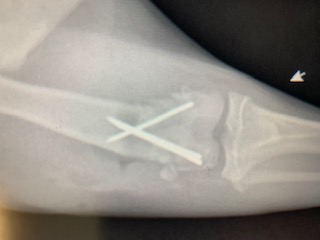

The Humane Society of Parkersburg reached out to Dr. Gandolf, who was able to surgically repair the femur- at a cost they could afford! The Animal Care Hospital of Reynoldsburg generously offered their operating room to help make this possible. This affordable alternative allowed the Humane Society of Parkersburg to save Marigold’s leg!

The Humane Society of Parkersburg was able to repair Marigold’s leg rather than amputate because of donations that fund these kinds of surgeries! Please consider giving TODAY to help Marigold and other dogs keep their legs!!